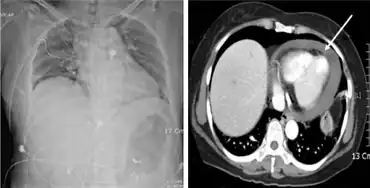

Hemopericardium refers to blood in the pericardial sac of the heart. It is clinically similar to a pericardial effusion, and, depending on the volume and rapidity with which it develops, may cause cardiac tamponade.[1]

Hemopericardium can be diagnosed with a chest X-ray or a chest ultrasound, and is most commonly treated with pericardiocentesis.[6] While hemopericardium itself is not deadly, it can lead to cardiac tamponade, a condition that is fatal if left untreated.[6]

Hemopericardium can be diagnosed using echocardiography, a cardiac ultrasound.[6] Chest X-rays are also often taken when hemopericardium is suspected and would reveal an enlarged heart.[6]